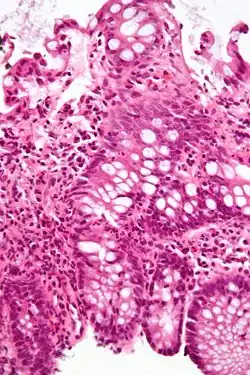

![]() Micrograph of the small intestine mucosa showing the intestinal glands - bottom 1/3 of image. H&E stain. | |

In histology, an intestinal gland (also crypt of Lieberkühn and intestinal crypt) is a gland found in between villi in the intestinal epithelial lining of the small intestine and large intestine (or colon). The glands and intestinal villi are covered by epithelium, which contains multiple types of cells: enterocytes (absorbing water and electrolytes), goblet cells (secreting mucus), enteroendocrine cells (secreting hormones), cup cells, myofibroblast, tuft cells, and at the base of the gland, Paneth cells (secreting anti-microbial peptides) and stem cells.

Structure

Intestinal glands are found in the epithelia of the small intestine, namely the duodenum, jejunum, and ileum, and in the large intestine (colon), where they are sometimes called colonic crypts. Intestinal glands of the small intestine contain a base of replicating stem cells, Paneth cells of the innate immune system, and goblet cells, which produce mucus.[1] In the colon, crypts do not have Paneth cells.[2]